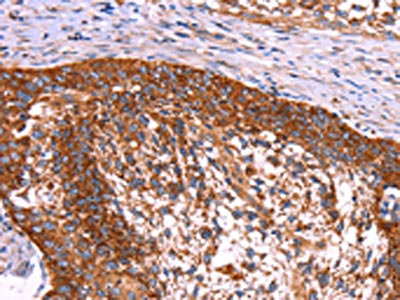

IHC (Immunohistochemistry)

(The image on the left is immunohistochemistry of paraffin-embedded Human cervical cancer tissue using AAA239650(ABI1 Antibody) at dilution 1/40, on the right is treated with synthetic peptide. (Original magnification: ×200))